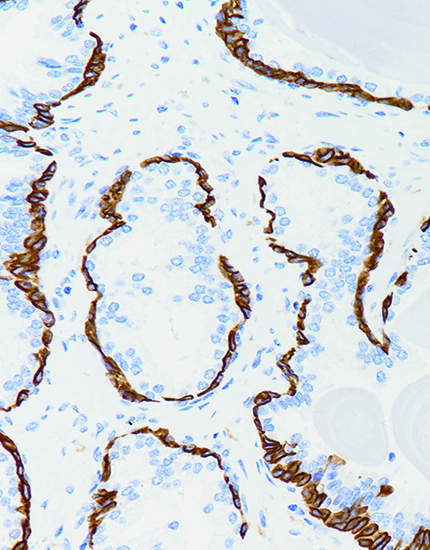

肾上腺皮质腺瘤,Melanoma(HMB45)染色,细胞质阳性,DAB显色